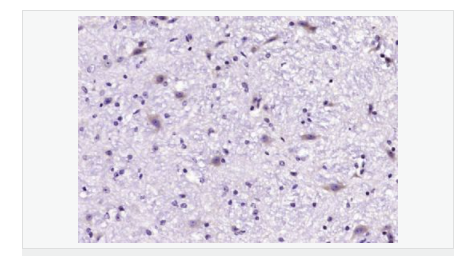

產(chǎn)品介紹GLRB (Glycine receptor beta) is a neurotransmitter-gated ion channel concentrated within the spinal cord and brainstem. Expression is also observed in several upper brain regions including the cortex, cerebellum, hippocampus and amygdala. Binding of glycine to GLRB increases the chloride conductance and thus produces hyperpolarization (inhibition of neuronal firing), controlling spinal reflexes and locomotor behavior.